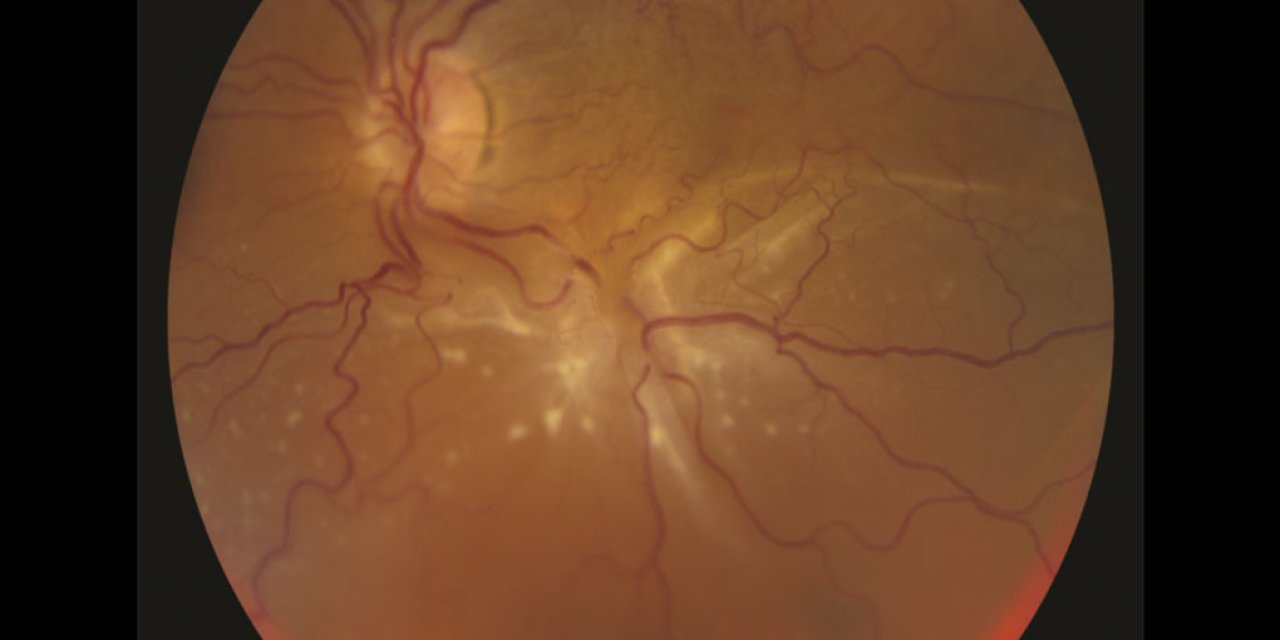

Görme sağlığının geleceği İzmir’de konuşuldu